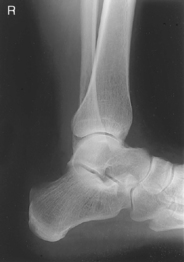

• Recumbent, affected side down, affected knee partially flexed

• Dorsiflex foot 90° to leg if patient can tolerate.

• Place support under knee as needed for true lateral of foot and ankle.